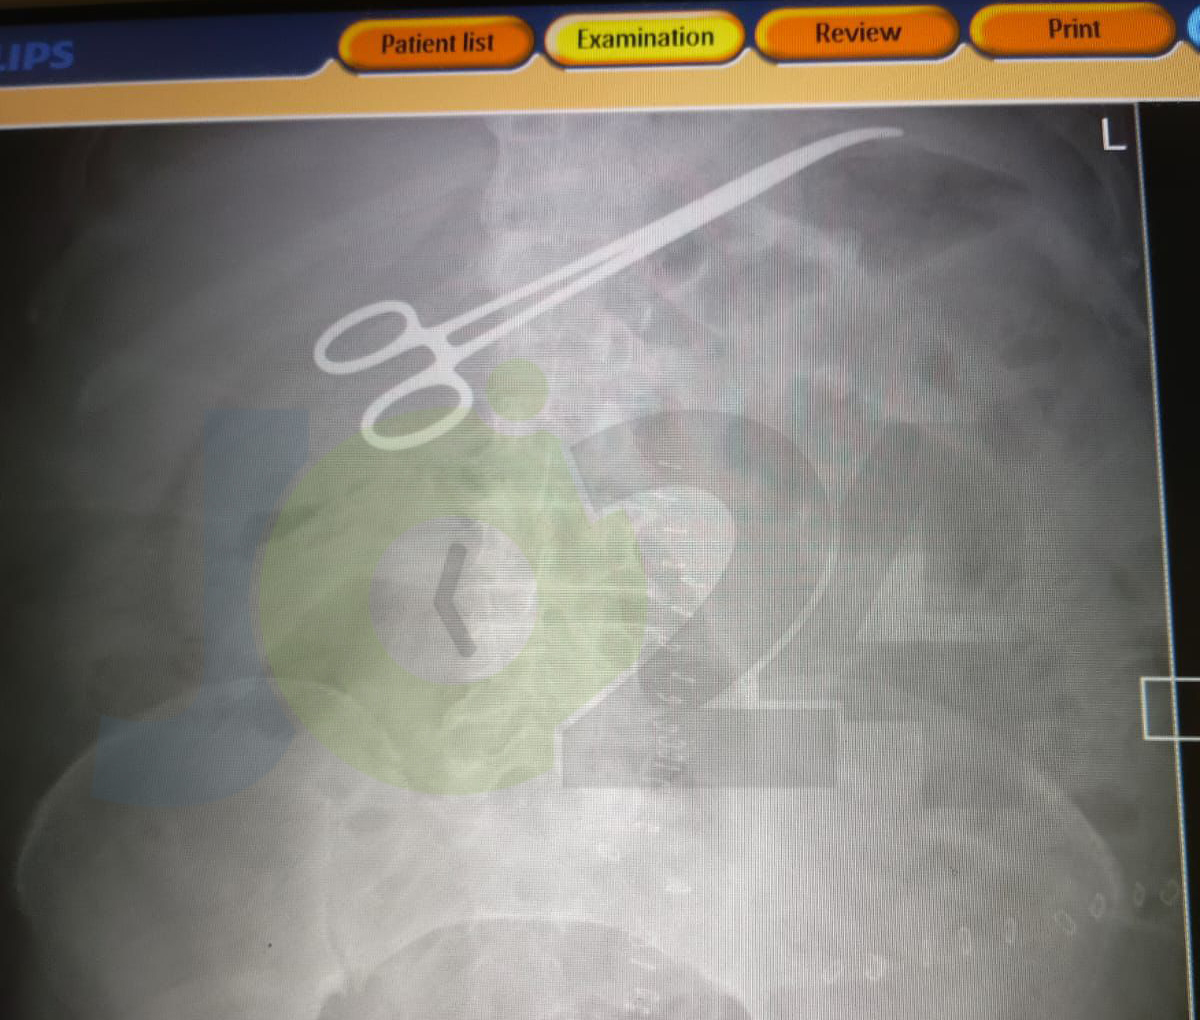

• إجراء 182 قسطرة "إنقاذ حياة" الشهر الماضي ضمن بروتوكول الجلطات القلبية